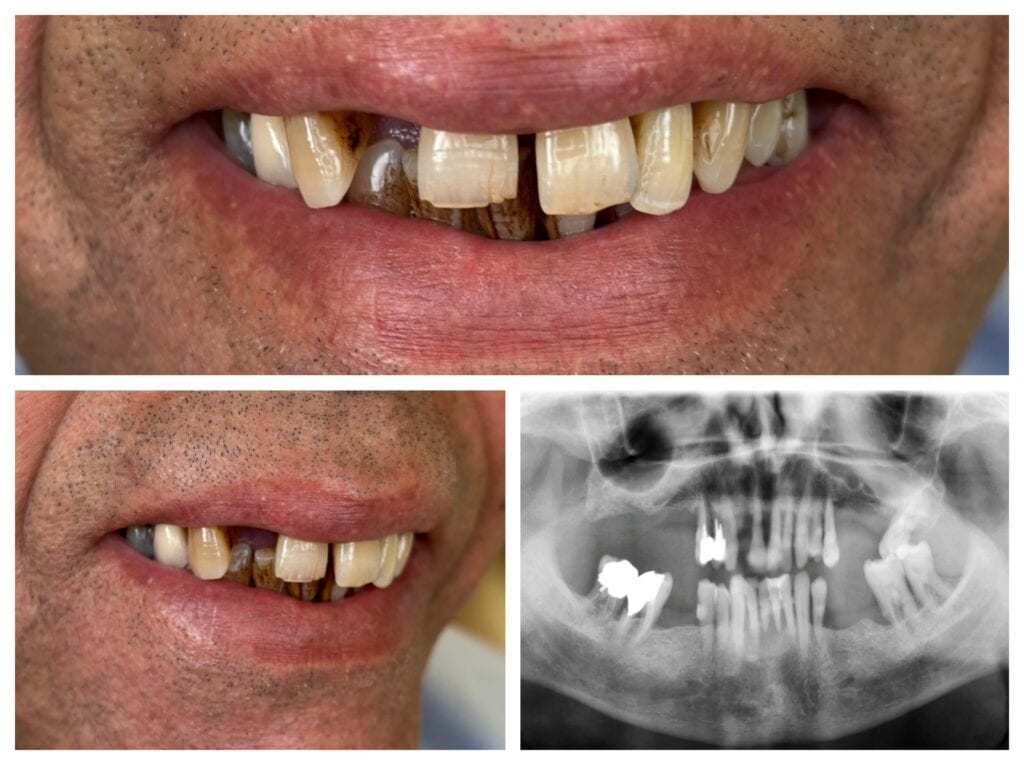

Zirconia All-on-4 fixed prosthesis before / after

The Diagnosis: When Saving Teeth is No Longer an Option

Many people postpone dental treatment because they fear drastic procedures or the thought of total tooth loss. Our patient’s story began with a classic yet highly educational situation: due to extensive periodontal disease (periodontitis) and advanced decay, the 23 teeth remaining in the oral cavity unfortunately had to be declared unsalvageable.

During the diagnostic phase (CBCT and physical examination), we faced the following conditions:

- Bone loss in the posterior region: The patient had lost their back molars years ago, leading to significant bone resorption (atrophy) in those areas.

- Adequate bone in the anterior region, around the remaining teeth: Fortunately, there was sufficient and high-quality bone in the front region to ensure the stable anchoring of implants.

Initial state: missing teeth, periodontal disease, and decay